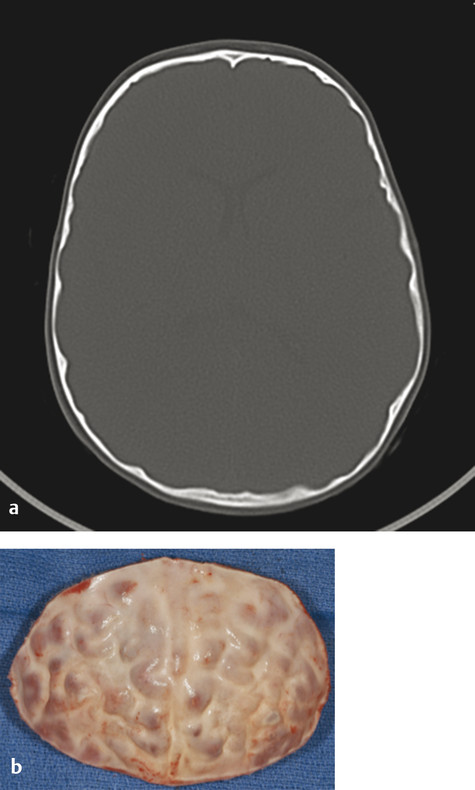

Direct ICP monitoring is invasive and rarely used for routine screening. Moreover, the measurement is only a snapshot in time: a normal pressure measurement early in life does not imply that it will remain so as the brain continues to grow. Consequently, many surgeons resort to noninvasive, but less reliable, indicators of ICP. Conventional clinical symptoms of acute ICP elevation, such as headache, somnolence, and dizziness, are often lacking, even in severely affected children. Papilledema and subsequent optic atrophy are strongly suggestive of elevated ICP but have limited sensitivity in children younger than 8 years. As optic atrophy progresses, the disk becomes pale, the capillaries and hyperemia disappear, and significant secondary arteriolar narrowing occurs (Fig. 1‑3). Reducing ICP can reverse early changes, but more advanced degeneration may be permanent. Radiographic evidence suggestive of elevated ICP includes loss of subdural space, often with effacement of the basal cisterns and vertex sulci, ventricular compression, and scalloping of the cranial endocortex. This latter finding has been termed the “copper beaten” skull and can be visualized on both conventional radiography and CT (Fig. 1‑4). It is a late finding caused by pressure remodeling of the inner table of the skull by the cerebrum. The correlation of this finding with elevation in the ICP has been questioned.